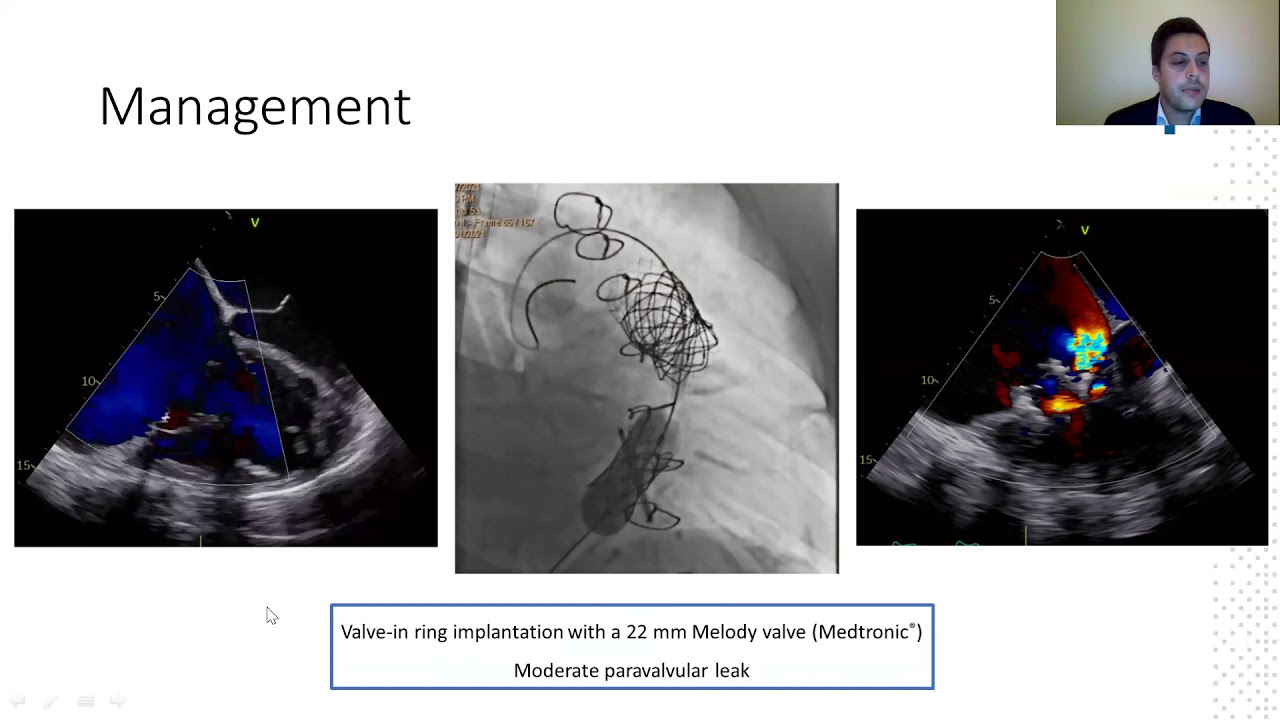

Mitral valve repair and replacement

Percutaneous balloon valvuloplasty for bioprosthesis mitral valve dysfunctional

By: Pabla Cataldo, Insituto Nacional del Torax, Santiago, Chile